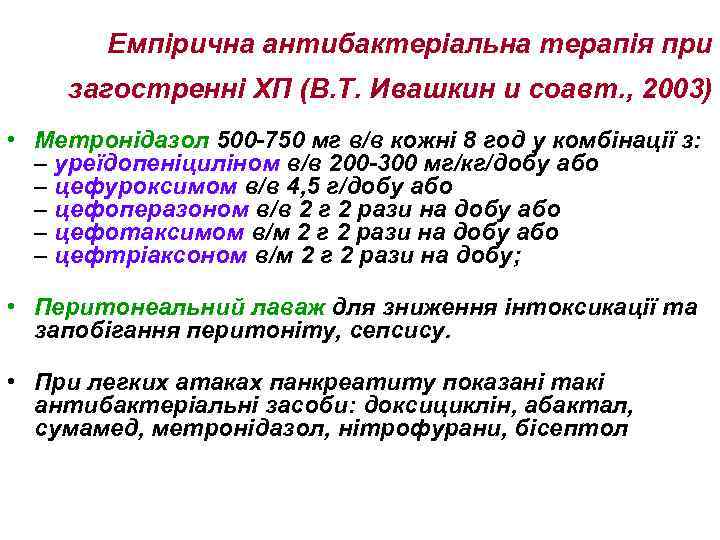

Емпірична антибактеріальна терапія при загостренні ХП (В. Т. Ивашкин и соавт. , 2003) • Метронідазол 500 -750 мг в/в кожні 8 год у комбінації з: – уреїдопеніциліном в/в 200 -300 мг/кг/добу або – цефуроксимом в/в 4, 5 г/добу або – цефоперазоном в/в 2 г 2 рази на добу або – цефотаксимом в/м 2 г 2 рази на добу або – цефтріаксоном в/м 2 г 2 рази на добу; • Перитонеальний лаваж для зниження інтоксикації та запобігання перитоніту, сепсису. • При легких атаках панкреатиту показані такі антибактеріальні засоби: доксициклін, абактал, сумамед, метронідазол, нітрофурани, бісептол

Емпірична антибактеріальна терапія при загостренні ХП (В. Т. Ивашкин и соавт. , 2003) • Метронідазол 500 -750 мг в/в кожні 8 год у комбінації з: – уреїдопеніциліном в/в 200 -300 мг/кг/добу або – цефуроксимом в/в 4, 5 г/добу або – цефоперазоном в/в 2 г 2 рази на добу або – цефотаксимом в/м 2 г 2 рази на добу або – цефтріаксоном в/м 2 г 2 рази на добу; • Перитонеальний лаваж для зниження інтоксикації та запобігання перитоніту, сепсису. • При легких атаках панкреатиту показані такі антибактеріальні засоби: доксициклін, абактал, сумамед, метронідазол, нітрофурани, бісептол